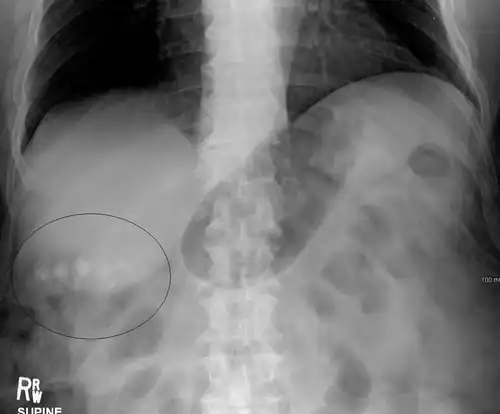

Gallstone ileus

Large gallstones can potentially erode through the gallbladder wall and into the neighboring small intestine. This large stone then travels through the small intestine until it is too narrow for the stone to continue, causing a small bowel obstruction. This obstruction often occurs at previous surgical sites or at the ileocecal valve (the portion of the bowel where the small intestine meets the large intestine). The patient presents with the inability to defecate or pass gas, nausea, vomiting, and severe abdominal pain.[14]